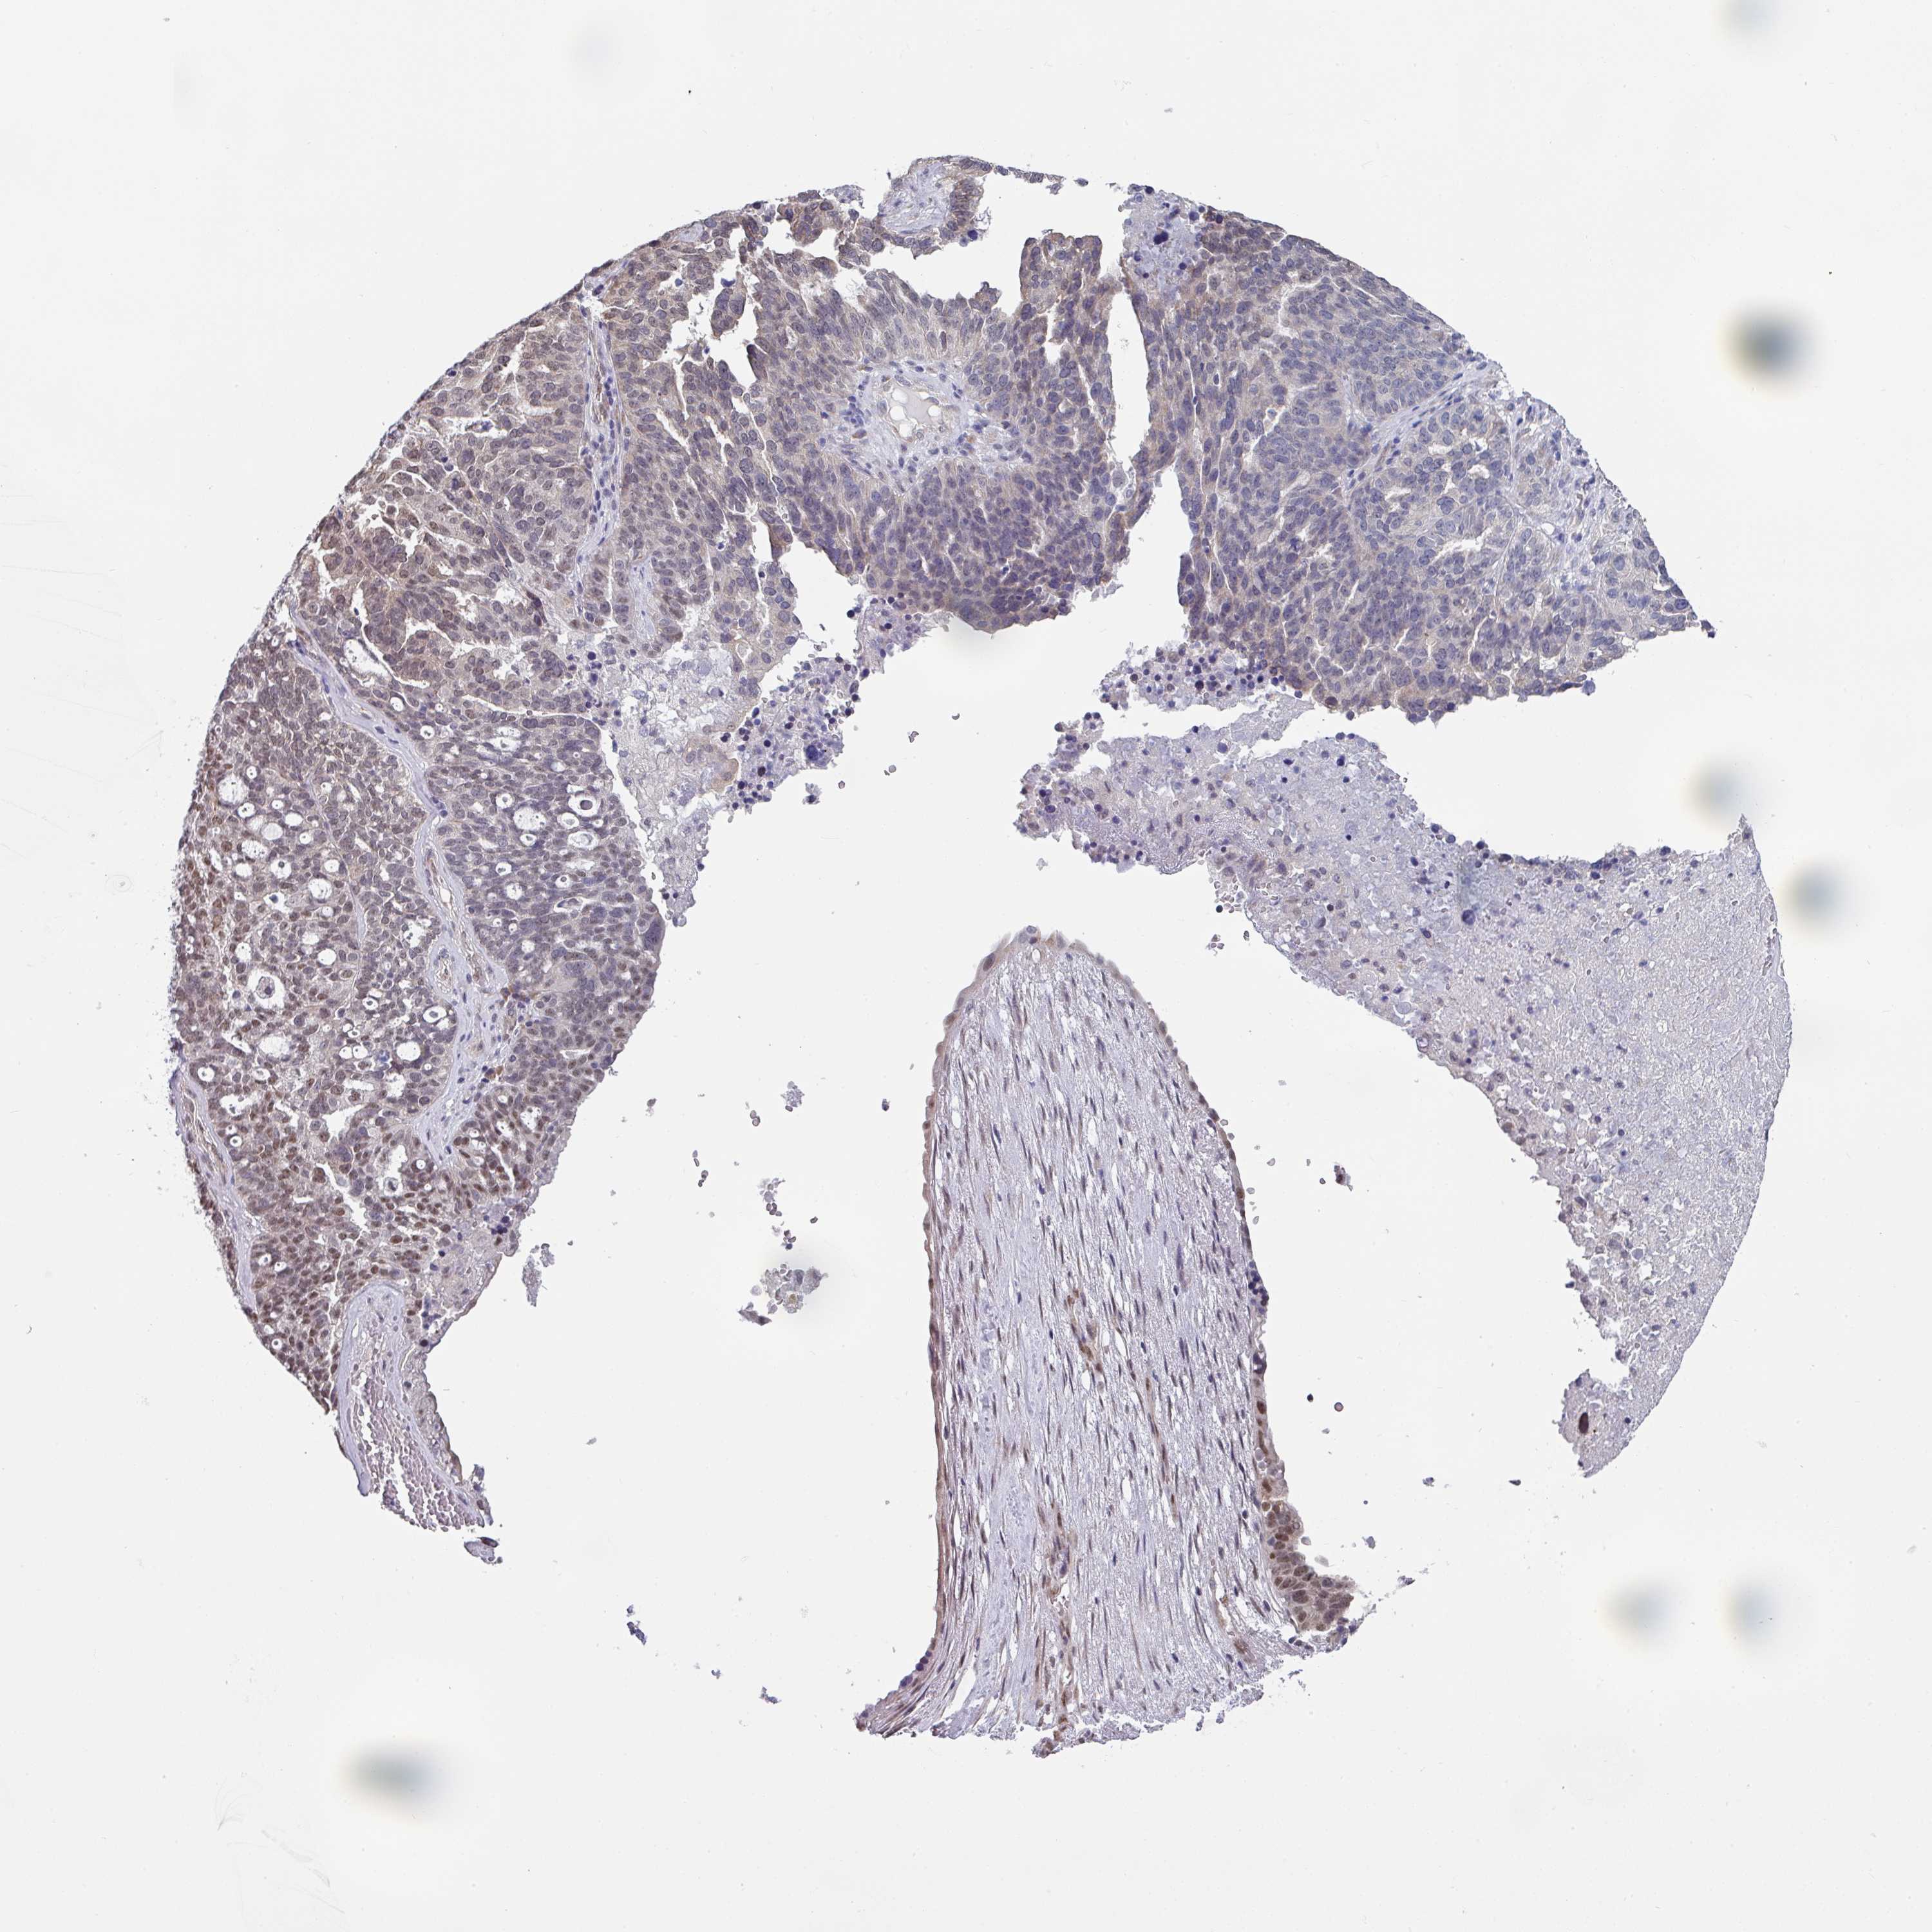

OVARIAN CANCER - Protein expressioni

A mouse-over function shows sample information and annotation data. Click on an image to view it in a full screen mode. Samples can be filtered based on level of antibody staining by selecting one or several of the following categories: high, medium, low and not detected. The assay and annotation is described here.

Note that samples used for immunohistochemistry by the Human Protein Atlas do not correspond to samples in the TCGA dataset.

Antibody stainingi

Antibody staining in the annotated cell types in the current human tissue is reported as not detected, low, medium, or high, based on conventional immunohistochemistry profiling in selected tissues. This score is based on the combination of the staining intensity and fraction of stained cells.

Each image is clickable and will lead to virtual microscopy that enables deeper exploration of all samples and also displays staining intensity scores, fraction scores and subcellular localization as well as patient and tissue information for each sample.

Antibody HPA050289

Staining

High

Medium

Low

Not detected

Intensity

Strong

Moderate

Weak

Negative

Quantity

>75%

75%-25%

<25%

None

Location

Nuclear

Cytoplasmic/membranous

Cytoplasmic/membranous,nuclear

Cystadenocarcinoma, serous, NOS

Carcinoma, NOS

Cystadenocarcinoma, mucinous, NOS

Carcinoma, endometroid